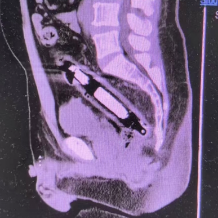

王先生的ct图及取出的异物图。

长沙市中医医院肛肠科副主任医师李心茹检查确定该异物为近20厘米长的圆柱状金属物。考虑到金属物质坚硬,若不及时取出,极有可能扎破肠道引发穿孔,治疗团队当即为王先生制定紧急手术方案。在快速完善各项术前准备、麻醉成功后,手术当日顺利开展。最终,医生成功将金属异物取出,术后王先生恢复良好。